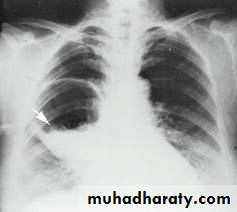

Fall from the 2nd floor